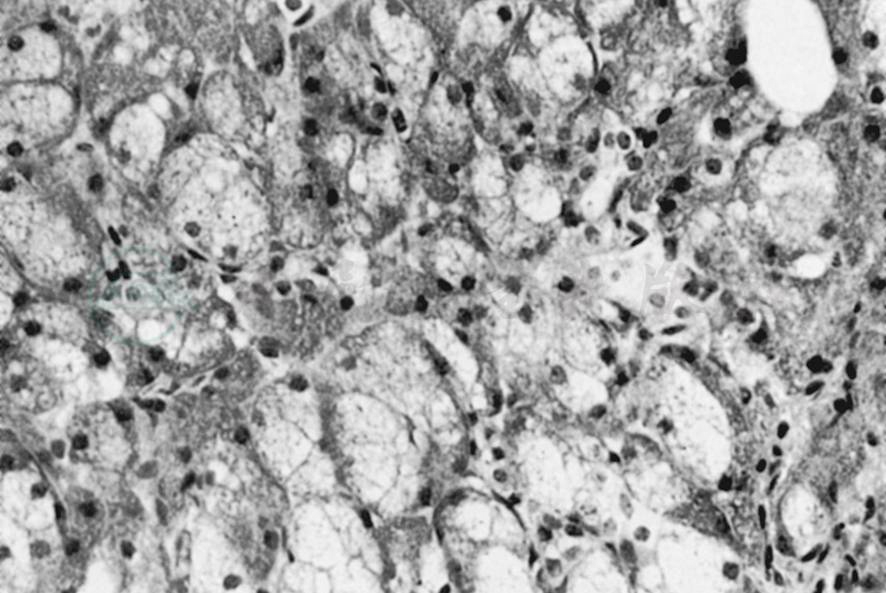

主要病变见于浆液性腺泡,光镜下见浆液性腺泡增大,约为正常腺泡的2~3倍,腺泡细胞之间界限不清,融成一片,腺泡细胞的胞质内有许多小空泡形成,腺泡细胞顶端的酶原颗粒消失;胞核比正常小,位于细胞基部。闰管及分泌管一般均正常。间质结缔组织可出现玻璃样变和水样变性,有的腺泡消失而被脂肪组织所取代(图1)。

图1唾液腺良性肥大

腮腺腺泡增大,腺泡内有许多小空泡形成,胞核小,位于基部